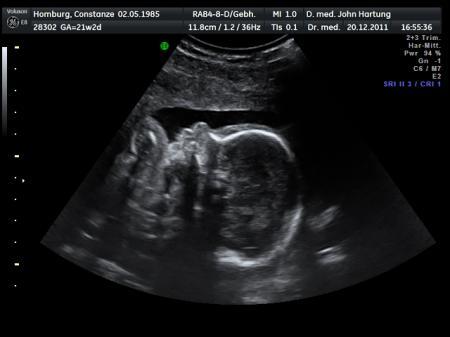

Hallo meine Lieben, Ich hatte gestern mein FD Termin und es ist alles in Ordnung. Wir sind super happy. Die 3D Bilder sehen ja aber teilweise ganz schön gruselig aus. Findet ihr das auch?

Bild zu FD - Forum für April - Mamis